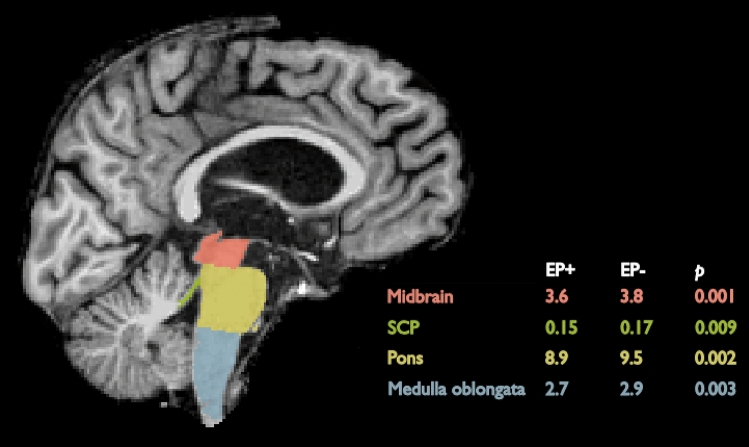

Next, we focused on the volumes of the subcortical GM structures. Considering the whole patient group, EP + patients showed significantly lower volumes in the right putamen (p = 0.002), bilateral globus pallidum (p = 0.002, p = 0.042; right (R), left (L)), right ventral diencephalon (p = 0.002), and brain stem (p < 0.001) when compared to the EP- patients. In further examination, the brain stem was segmented into subparts. All parts showed significantly lower volumes in the EP + group; medulla oblongata (p = 0.003), pons (p = 0.002), superior cerebellar peduncle (SCP) (p = 0.009), and midbrain (p = 0.001) (Tables 1 and 2). Other subcortical GM regions did not show any differences between the EP + and EP- groups.

In the subgroup of only bvFTD patients, the results were partly similar and the EP + patients showed significantly lower volumes when compared to the EP- patients. The most prominent difference was observed in the brain stem (p = 0.001) and its subparts; medulla oblongata (p = 0.004), pons (p = 0.002), SCP (p = 0.001), and midbrain (p = 0.001), followed by right globus pallidum (p = 0.027) and bilateral ventral diencephalon (p = 0.004, p = 0.028; R,L). Other subcortical GM regions in the bvFTD subgroup did not show any difference between the EP + and EP- groups.

Here, we report an association between EP symptoms and brainstem atrophy in patients suffering from FTD spectrum disorders in general, and also specifically in the bvFTD patients. To the best of our knowledge, these are novel findings. EP symptoms in Parkinson’s disease patients are known to originate from atrophy of the basal ganglia in the midbrain (substantia nigra pars compacta). These patients are neuropathologically characterized mainly by α-synucleopathy. Also, PSP and CBD usually present EP symptoms, but in these disorders, the main underlying neuropathology is tauopathy, which is a neuropathology commonly detected in the FTD spectrum disorders [ref. 17]. Thus, different molecular neuropathologies could underlie the different topographical propagation of the neuropathological changes in the brain of these patients. In PSP, atrophy in the SCP and in the cerebrum at the level of the subthalamic nucleus (STN) is detected, whereas the SCP and STN are normal in Parkinson’s disease brain [ref. 18]. We also found hypometabolism in the SCP of the EP + bvFTD patients compared to EP- bvFTD patients. This finding could indicate that the EP symptoms of the FTD-related tauopathies originate from atrophy in the more caudal areas of the brainstem compared to patients with Parkinson’s disease. According to our data, the hypometabolism was asymmetrical between the two hemispheres. The asymmetry of neuropathology in post-mortem bvFTD brain has been reported in 2018 [ref. 19], but the underlying cause of this remains to be explored (Fig. 2).

The previously reported neuroimaging findings in bvFTD patients are diverse and vary according to the disease-causing genetic mutation and underlying neuropathology. Our findings suggest that hypometabolism in the brain stem, SCP, and left temporal and frontal lobe as well as volume loss in the brain stem, globus pallidum, putamen, and SCP are linked to EP symptoms in bvFTD. The C9orf72 repeat expansion has been reported to associate with atrophy of the more posterior and subcortical brain areas, including cerebellum, occipital and parietal cortex, thalamus, and the striatum, even at the presymptomatic phase [ref. 20–ref. 26]. Up to 14–48% of the patients carrying the C9orf72 repeat expansion exhibit parkinsonism [ref. 27]. In Finland, a vast majority of familial bvFTD is caused by the C9orf72 repeat expansion, which may at least partially explain our present findings. However, we observed prominent atrophy of the brain stem in the EP + bvFTD patients. This is not a common site of atrophy in the bvFTD patients, although it is often detected in CBD [ref. 28]. One explanation for this could be that the thalamus is one of the first structures to be affected by bvFTD [ref. 20, ref. 21, ref. 24, ref. 29]. As thalamus is closely connected to the brain stem nuclei, its dysfunction could lead to Wallerian-like degeneration of the brain stem tracts and nuclei. The reason why only some but not all bvFTD patients develop brain stem atrophy remains to be elucidated (Fig. 3).